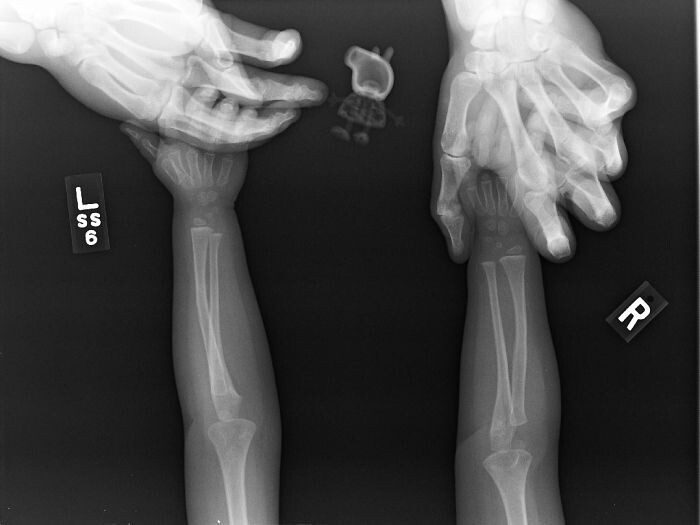

«Я дантист, но рентгеновские снимки детей 6-12 лет меня немного пугают до сих пор»